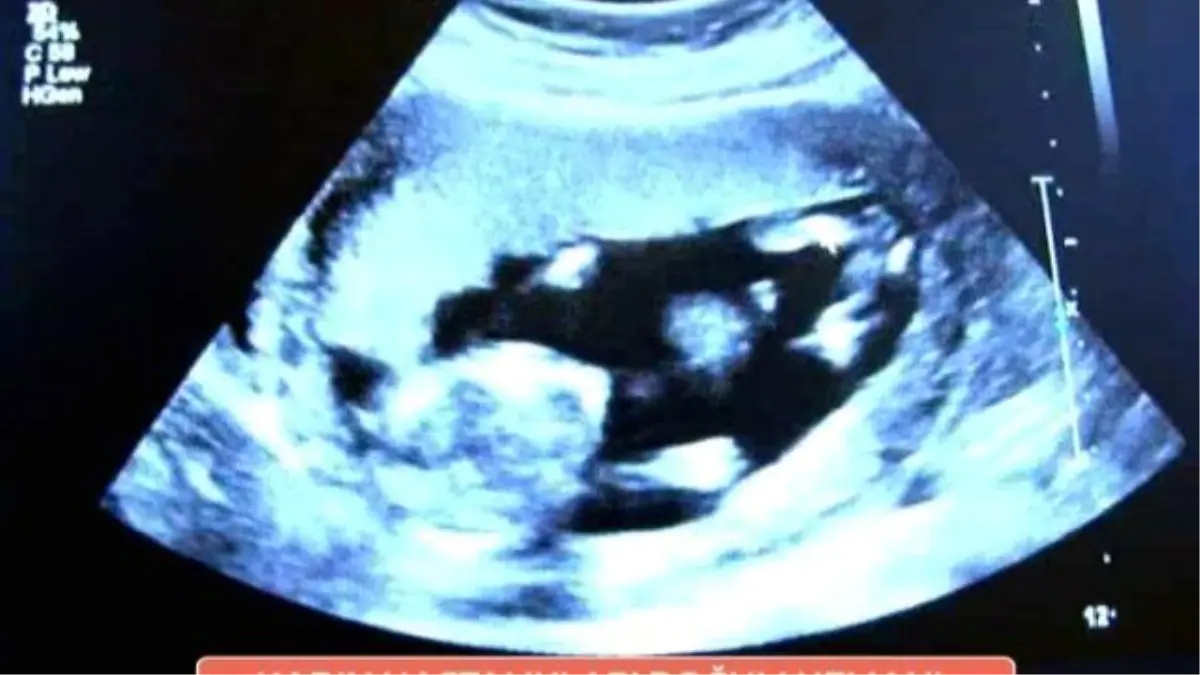

Kadın Hastalıkları ve Doğum Uzmanı Op.Dr. Zeki SALAR gebelik haftası hesaplama hakkında bilgi veriyor.